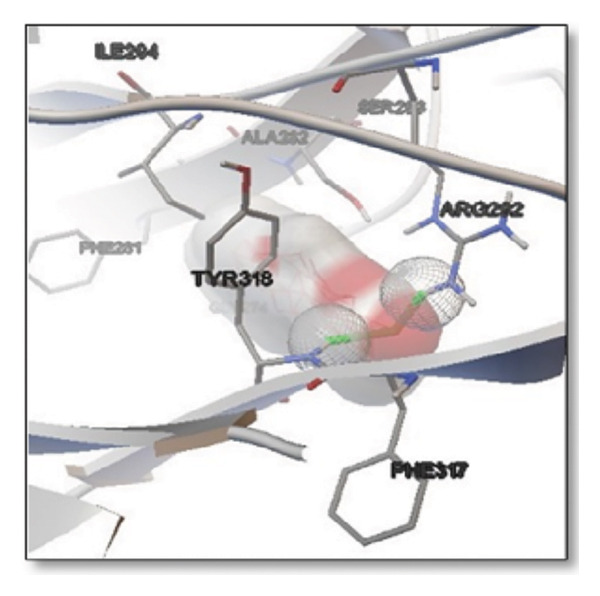

For the tau protein repeat domain, ginkgolide recorded a strong binding energy of −10.63 kcal/mol, with a key stabilizing interaction involving HIS329. This interaction was characterized by a D–A distance of 3.05 Ǻ and an excellent angle of 170.04°. Other top binding compounds included ginsenosides (−6.28 kcal/mol), also interacting with HIS329 and PRO364, and galantamine (−5.47 kcal/mol), forming bonds with VAL337 and VAL339. Berberine bound at −5.33 kcal/mol via GLN351. Apigenin exhibited favorable interaction with the tau repeat domain via a hydrogen bond with ILE 328 (D–A: 2.91 Ǻ; angle 161.21°), highlighting the high quality of the interaction. Among the reference drugs, donepezil bound at −5.34 kcal/mol. Figure 5 details the binding characteristics for tau protein.

Figure 7Molecular docking analysis of ginkgolide interactions with Alzheimer’s disease‐related proteins: Molecular docking analysis of ginkgolide’s interactions with four key proteins—sortilin, clusterin, amyloid‐beta peptide, and tau protein. Column (a, d, g, j) shows the receptor–ligand interaction surface, providing a visual representation of how ginkgolide binds to the active site of each protein. The second column (b, e, h, k) depicts the secondary structure and ligand interactions, offering insights into the specific amino acid residues and structural motifs convoluted in binding. The third column (c, f, i, l) presents the LigPlot+ interaction diagram, providing a 2D schematic of the ligand–protein interactions, highlighting hydrogen bonds and hydrophobic contacts between ginkgolide and the surrounding amino acids of the binding site.(a)(b)(c)(d)(e)(f)(g)(h)(i)(j)(k)(l)

Multiplatform docking (MTi‐AutoDock, DockThor, and Webina) and PLIP analysis confirmed consistent binding orientations and affinities. Key interactions (H‐bonds, hydrophobic contacts) aligned with known active‐site residues. Redocking RMSD values (< 2 Å) indicated high pose reproducibility. Binding‐site validation confirmed biologically relevant cavities.